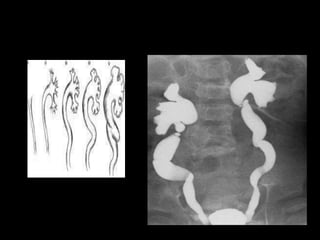

Goldman & Sander classification (Based on findings at retrograde urethrography)

• Type I injury

 Rupture of the puboprostatic ligaments which stretches the prostatic

urethra

 Continuity of the urethra is maintained

 Type II injury (15%)

The membranous urethra is torn above an intact

urogenital diaphragm, which prevents contrast material

extravasation from extending into the perineum

 Type III injury (MC)

The membranous urethra is ruptured but the injury extends into the

proximal bulbous urethra because of laceration of the urogenital

diaphragm

Extravasation not only into the pelvic extraperitoneal space but also

into the perineum.

• Type IV

Bladder neck injury with extension to the urethra.

Type V injury

Injury to the Anterior urethra - partial or complete.

Extravasation seen to penile soft tissue.